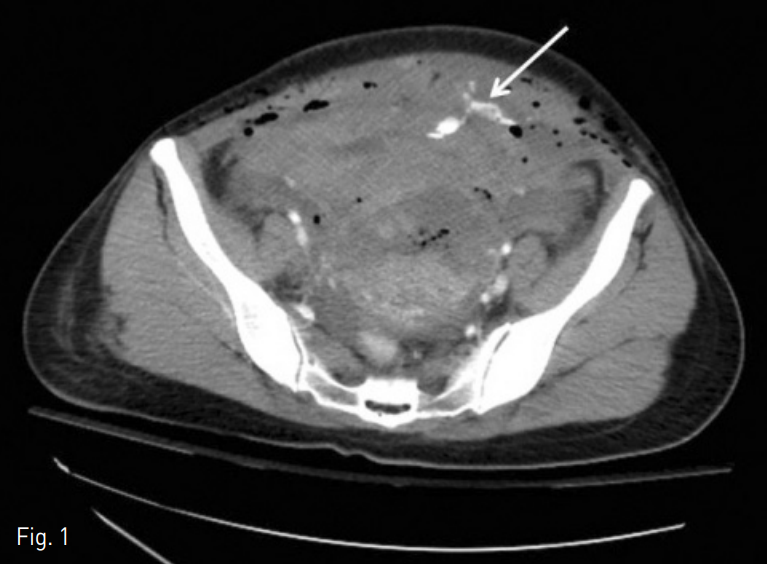

내원 당시 시행한 CT angiogram상 좌전방부 골반강에 조영제의 유출 (Fig. 1)과 주변부에 많은 양의 혈종 소견이 보였음. 하복벽에는 Cesarean section에 의한 것으로 보이는 피부종이 보였음.

Fig. 1

Axial CT angiogram shows an extravasation of the contrast media (arrow) in the left anterior pelvic cavity.